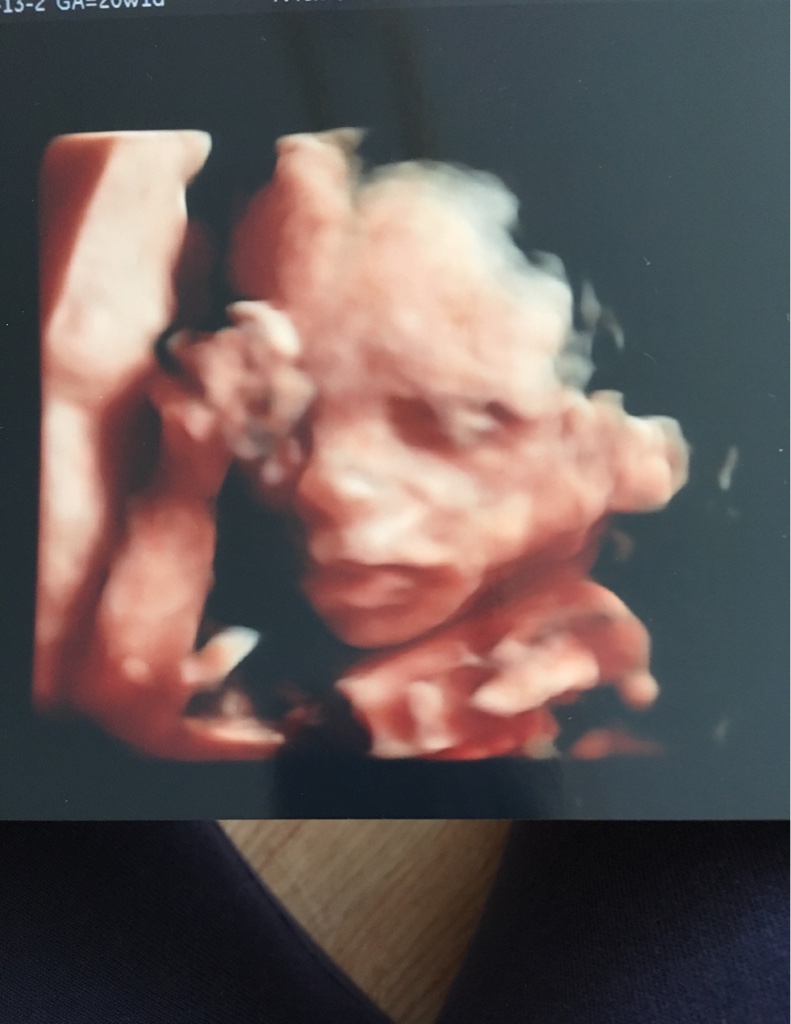

A o to mój syn :) mój wstydzioch :) dostaliśmy masę zdjęć i 3 filmy na pendrive :)

teraz popatrzylam na film i tam mam wlasnie napisane 4d ;)